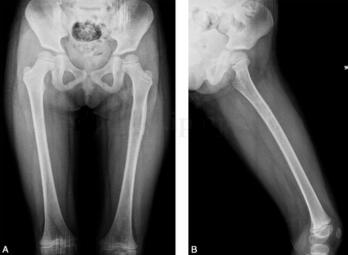

女,5岁,左下肢疼痛月余,近日加重,左下肢活动受限。病来无发热盗汗,无结核接触史。查体:左大腿肿胀,皮温略高,有压痛(图1、图2)。

图1 DR:左股骨上段略膨胀,局部骨皮质略增厚,其内可见小斑点状密度减低区,邻近软组织密度略增高

图2 MR:左股骨中上段髓腔内见长T1、长T2信号改变,局部肿胀增粗,左股骨局部外侧缘见层状骨膜反应,周围肌肉组织呈长T1、长T2信号改变